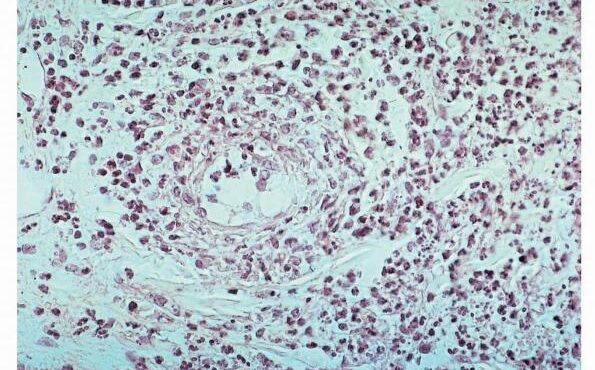

Necrobiois lipoidica diabeticorum = النخر الشحماني السكري Necrobiosis Lipoidica Necrobiosis lipoidica is an idiopathic disorder typified by indurated plaques of the shins . In 1966, in a large series, Muller and Winkelman reported that two thirds of patients with necrobiosis lipoidica had overt diabetes at the time of diagnosis {82}. Of the rest, all but […]